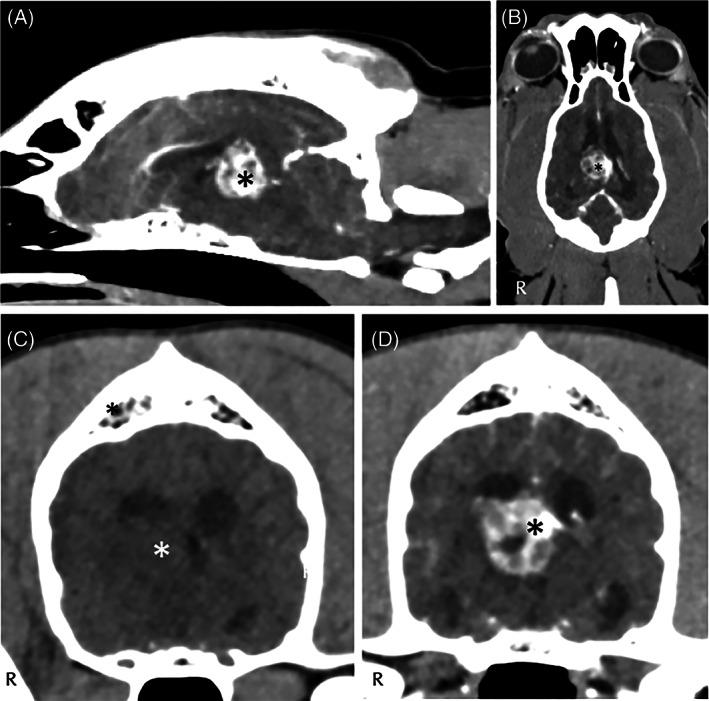

Four dogs met the inclusion criteria. Two dogs had bruxism while awake as a presenting complaint, whereas in the remaining 2 it was a clinical finding. All dogs had neuroanatomical localization consistent with a forebrain lesion, with diencephalic involvement in 3/4. The diagnostic evaluation was consistent with neoplasia (n = 2) and meningoencephalitis of unknown origin (n = 2), in 1 case accompanied by corpus callosum abnormality affecting the forebrain, in 3 dogs advanced imaging findings were suggestive of increased intracranial pressure. All dogs were euthanized.

4 只犬符合纳入标准。2 只犬因清醒时磨牙症作为主要症状就诊,其余 2 只为临床发现。所有犬均存在与前脑病变相一致的神经解剖学定位,4/4 的犬存在丘脑受累。诊断评估与肿瘤(n=2)和不明原因的脑膜脑炎(n=2)一致,1 例伴有影响前脑的胼胝体异常,3 只犬的高级影像学发现提示颅内压增高。所有犬均被安乐死。